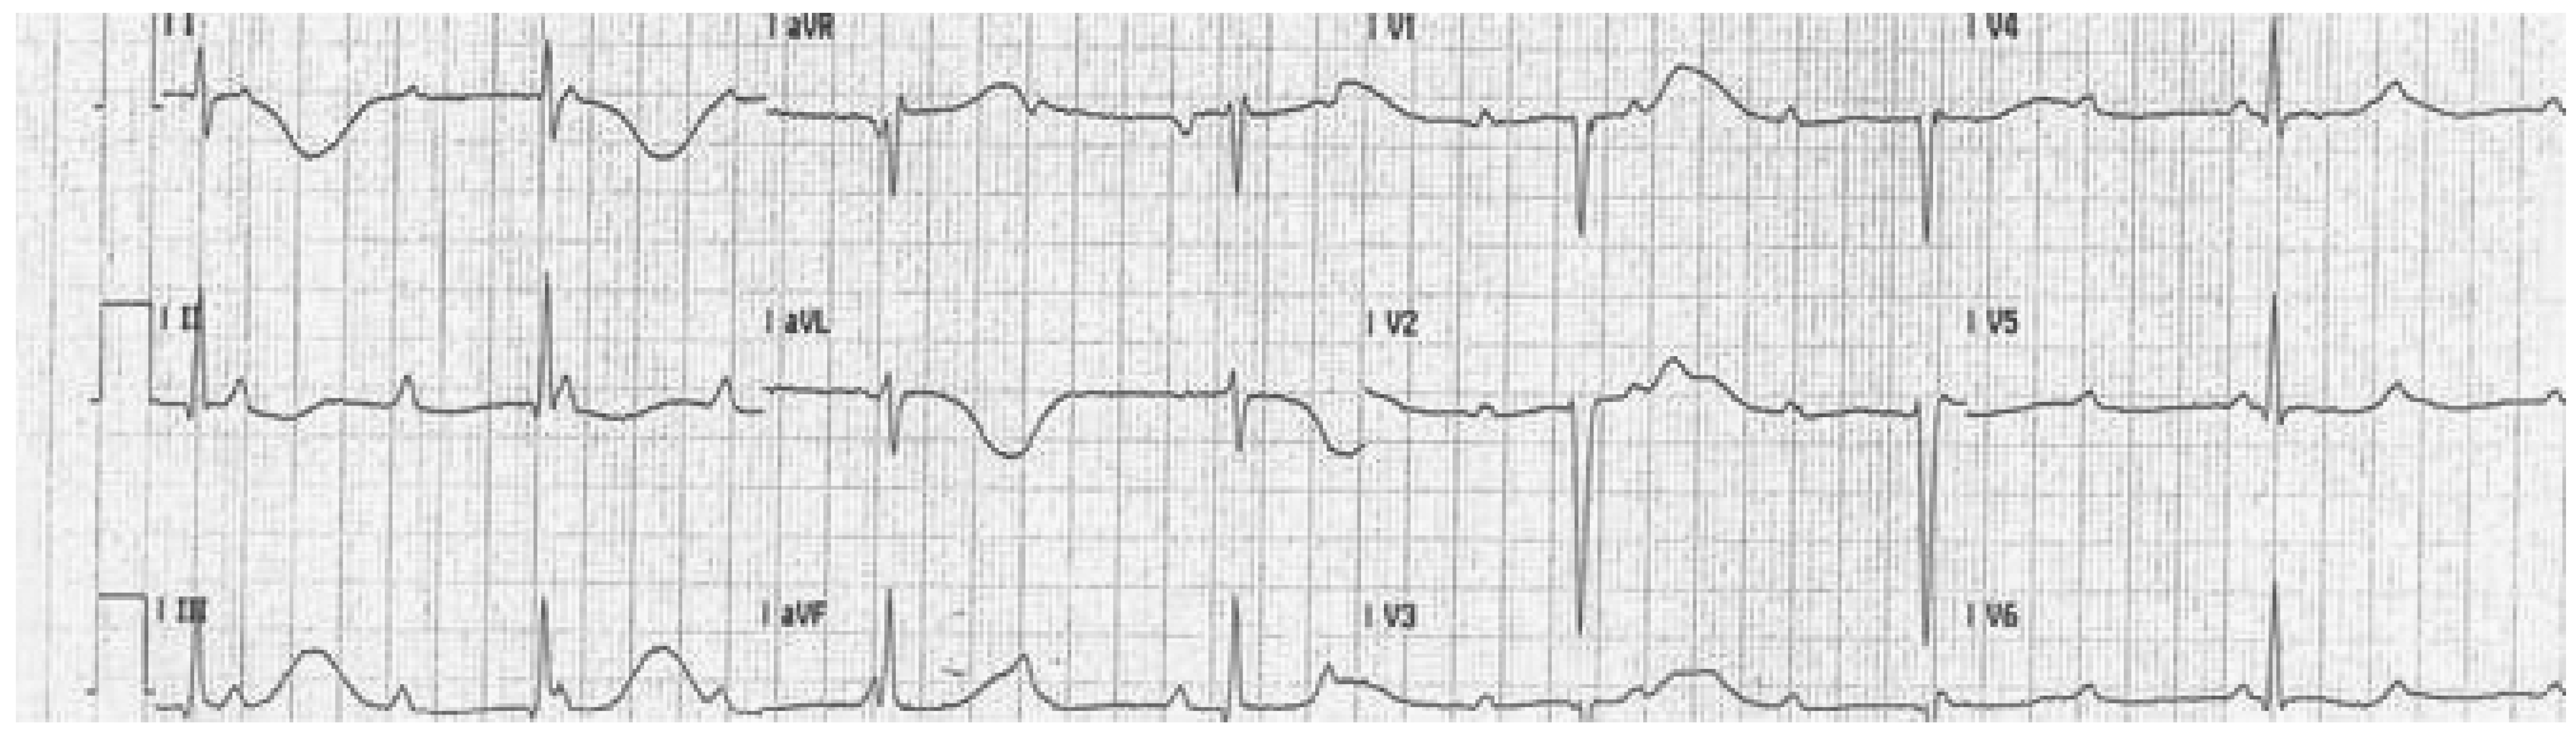

- Which pathology is displayed on the ECG?

- Are there any ECG clues for the cause of the cardiac arrest?